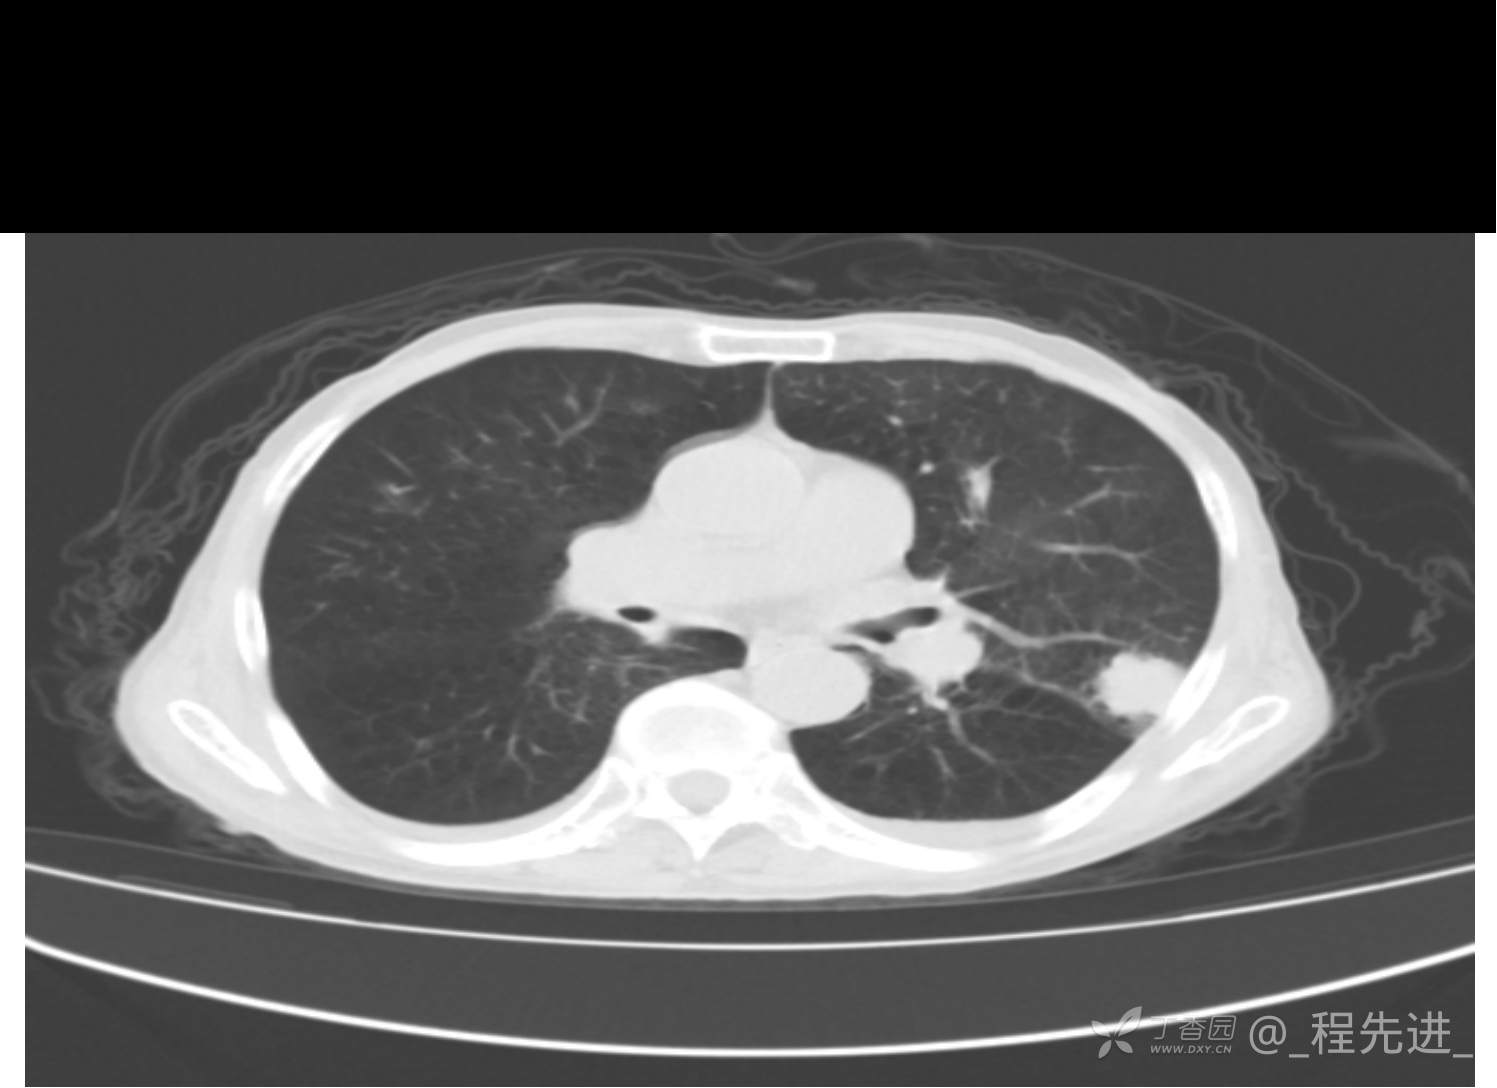

患者性别:男

患者年龄:81岁

简要病史:反复咳嗽、咳痰20余年,加重1周。两肺呼吸音低,可闻及散在干湿啰音。